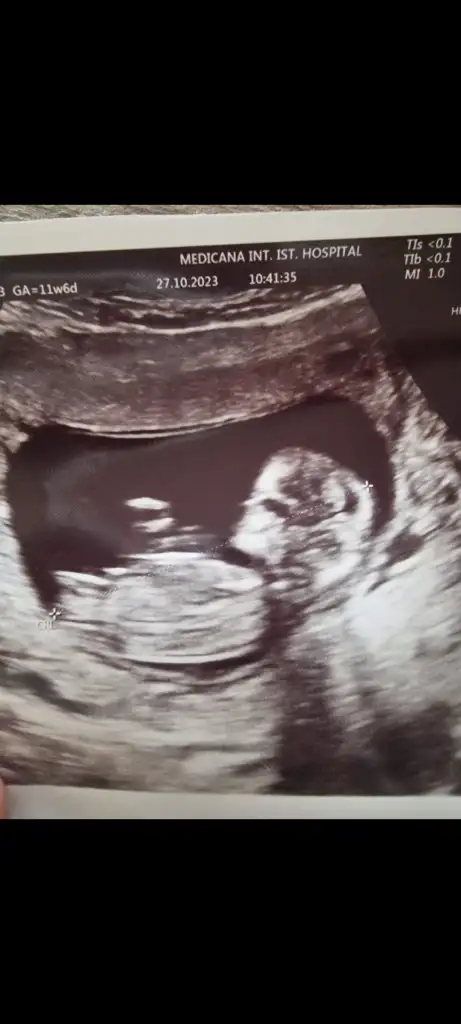

Merhaba 11 hafta 6 gün çatlamak üzereyim bana da bakabilir misiniz?Evet erkek bu bebiş

KızMerhaba 11 hafta 6 gün çatlamak üzereyim bana da bakabilir misiniz?

Bunlarada bakar mısınız lütfenNub teorisi benim 2 oğlumda doğru çıktı. Bu bebiş kıza benziyor

Nub teorisi benim 2 oğlumda doğru çıktı. Bu bebiş kıza benziyor